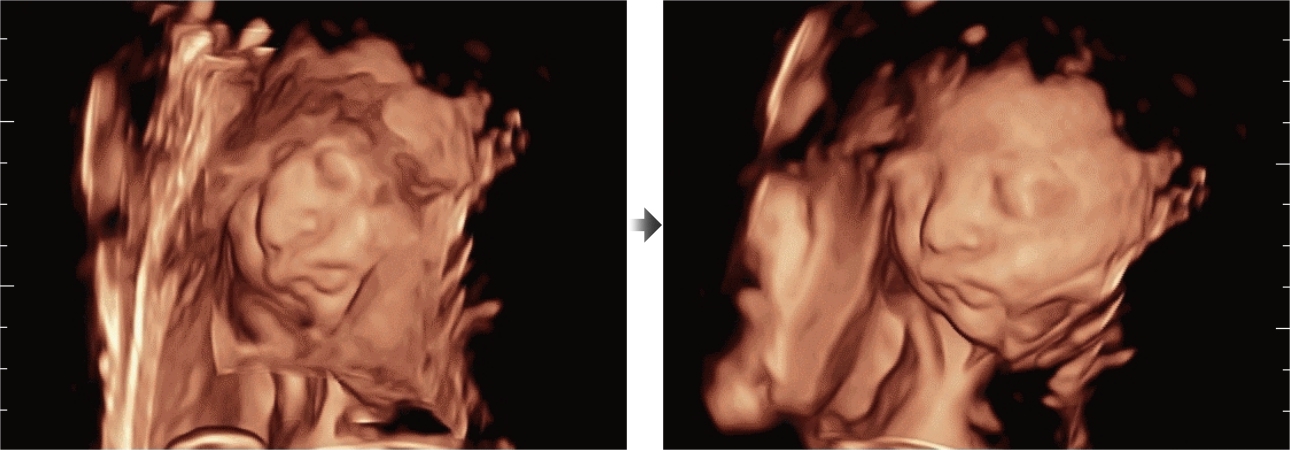

Además de la calidad de imagen de primer nivel, Resona?7 también mejora las capacidades de investigación clínica con el revolucionario V?Flow para la evaluación hemodinámica vascular y con la adquisición de planos más inteligente a partir de conjuntos de datos 3D para el diagnóstico del SNC fetal. Al combinar el funcionamiento multitáctil basado en gestos más intuitivo y todas las características clínicas esenciales, Resona?7 realmente lidera las novedades en innovación de ecografías.